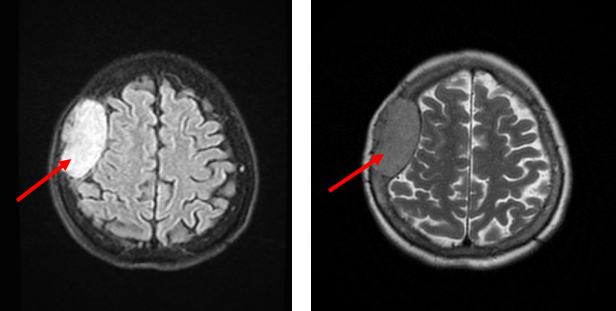

Hình 1: Hình ảnh MRI sọ não có tiêm thuốc đối quang từ: Ngoài trục vùng trán đỉnh phải và trong xương trán, đỉnh phải có khối tổn thương kích thước 68x36 mm, bờ đều, ranh giới rõ, sau tiêm ngấm thuốc mạnh đồng nhất, đẩy lồi da và phần mềm dưới da, đè đẩy nhu mô não nhưng không gây phù não.

Hình 2: Hình ảnh chụp cắt lớp vi tính sọ não không tiêm thuốc cản quang: Khối u đã được phẫu thuật, hình ảnh tụ dịch-máu-khí dưới màng cứng vùng trán phải.

Mô tả trong quá trình phẫu thuật: Khối u màng não trán đỉnh phải 6x3 cm, mật độ mềm, ranh giới rõ, khối u xâm lấn màng cứng, xoang tĩnh mạch, ăn khuyết xương sọ một diện 3x5 cm.